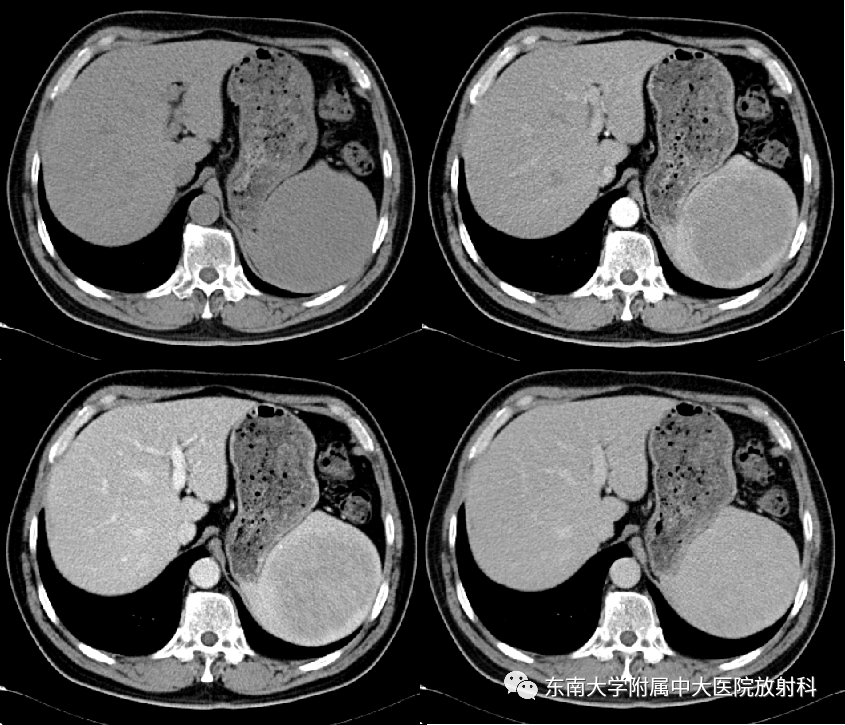

•女,48岁

•主诉:体检发现脾脏占位8天

•患者8天前于外院体检,查腹部彩超提示脾脏实性肿块

病例2

•男,55岁

•主诉:体检发现脾脏占位一周